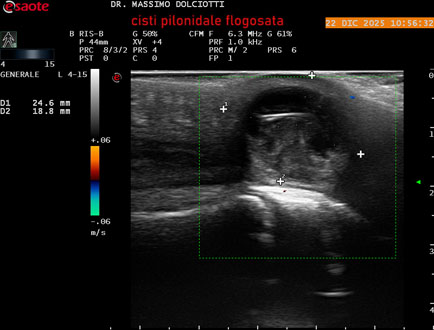

Strumento: Esaote MyLab Eight

Sonda: Lineare Multifrequenza 4-15 MHz

Età Paziente: M 29 anni

Motivazione dell'esame: da 3.giorni dolore, tumefazione ed arrossamento in regione coccigea

Commento all'esame: le immagini ed il video documentano formazione anecogena in sede coccige, delle dimensioni di 24,6 x 18,8 mm, da ricondurre a cisti pilonidale flogosata.

Conclusioni: cisti pilonidale flogosata (inflamed pilonidal cyst).

Presentazione: Dr. Massimo Dolciotti - Ancona